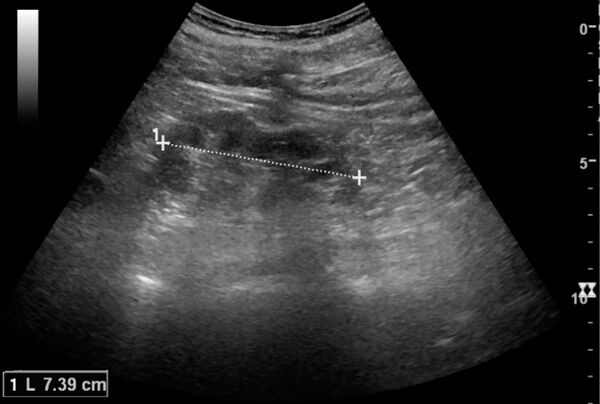

- ультразвуковое исследование (Ультразвуковое исследование) почек в фазе серозного воспаления при остром первичном пиелонефрите может не выявить патологических изменений в почках, в серозной фазе по УЗИ выявляется увеличение почек (или одной почки при одностороннем поражении) в размерах, уменьшение их подвижности при дыхании. При апостематозном пиелонефрите ультразвуковая картина такая же, как в фазе серозного воспаления (увеличение почек в размерах, ограничение их подвижности). Для карбункула почки при УЗИ характерно наличие гипоэхогенного участка без чётких контуров, иногда выбухание внешнего контура почки в этом месте. При формировании абсцесса почки при УЗИ определяется гипоэхогенный участок с чёткими контурами (капсула абсцесса) иногда с неоднородными анэхогенными участками в центре (жидкий гной). При выходе гнойного процесса за пределы капсулы почки (развитие паранефрита) при УЗИ определяется нечёткость паранефральной клетчатки с наличием в ней гипо- и анэхогенных компонентов.